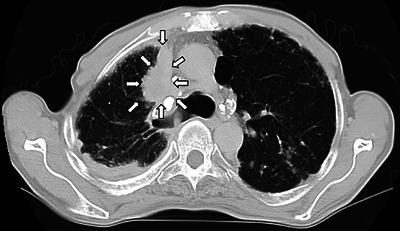

A 73-year-old man visited our hospital due to hyperintestinal peristalsis and diarrhea. He had been undergoing regular annual checkups for dust lung disease. Contrast-enhanced computed tomography scan showed edematous thickening of the rectal wall with contrast effect. A colonoscopy revealed a submucosal tumor-like protrusion in the Rb lesion of the rectum without neoplastic epithelial changes. Forceps biopsies of the overlying mucosa were non-diagnostic; however, endoscopic ultrasound-guided fine needle biopsy revealed that the specimen was poorly differentiated non-small cell invasive carcinoma. Then, we performed a chest computed tomography and a newly detected mass lesion in the upper lobe of the right lung. Based on immunohistochemical analysis and image findings, the patient was diagnosed with rectal metastasis from lung cancer. Subsequently, sputum cytology confirmed the diagnosis of lung adenocarcinoma. Rectal submucosal tumor-like protrusions are occasionally encountered. When a non-exposed rectal tumor is identified, it is important to differentiate metastatic diseases, consider endoscopic ultrasound-guided fine needle biopsy, and make a definitive diagnosis through detailed immunohistochemical evaluation and systemic imaging surveillance.

一名73岁男性因肠道蠕动亢进和腹泻前来我院就诊。他一直在接受尘肺病的定期年度检查。增强计算机断层扫描显示直肠壁水肿增厚并有造影剂增强效应。结肠镜检查发现直肠Rb病变处有一个黏膜下肿瘤样突起,无肿瘤上皮改变。对覆盖黏膜进行钳取活检未能明确诊断;然而,内镜超声引导下细针穿刺活检显示标本为低分化非小细胞浸润癌。随后,我们进行了胸部计算机断层扫描,在右肺上叶发现了一个新的肿块病变。基于免疫组化分析和影像学检查结果,该患者被诊断为肺癌直肠转移。随后,痰细胞学检查确诊为肺腺癌。直肠黏膜下肿瘤样突起偶尔会遇到。当发现未暴露的直肠肿瘤时,区分转移性疾病、考虑内镜超声引导下细针穿刺活检以及通过详细的免疫组化评估和全身影像学监测做出明确诊断非常重要。